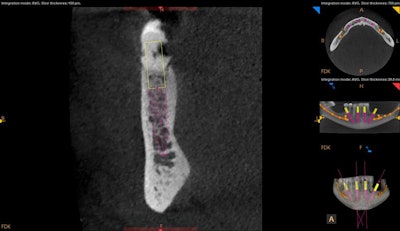

In the digital images below, you can see where CBCT technology and its associated treatment planning software allow us to "remove obstacles" by treatment planning angled implant placement and to "avoid obstacles" by treatment planning a prosthetic appliance that will decompress the inferior alveolar vein (IAV) nerve bundle. When combining a CBCT system with an intraoral scanner (CS 3700, Carestream Dental), I gain even more confidence in implant planning by merging a 3D scan with a digital impression for a prosthetic-driven approach to implants.

Mitra Sadrameli, DMD, states that treatment planning in 3D also allows for the consideration of greater specific patient-related information, resulting in surgical plans (and ultimately prosthetics) that are personalized for the patient.3 Consider the highly impacted maxillary molars that are evident in the above CBCT scans. A report from a maxillofacial oral radiologist (which I recommend with every scan) confirms that even though these are positioned superior to the level of the apices of the second molars, there is visual evidence that they are still in bone and present with no obvious pathologies, so they don't need specific treatment at this time. Periodic follow-up to evaluate stability of the impacted teeth may be considered.